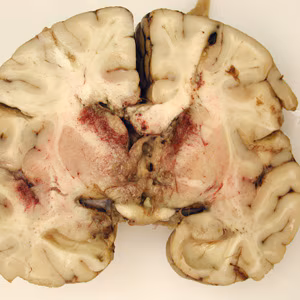

Case #223 – March, 2008

A seven-year-old, previously healthy child developed flu-like symptoms and rapidly progressive bulbar palsy, coma, and eventually death. Imaging revealed florid ventriculitis. A viral etiology was initially suspected. The autopsy revealed extensive necrotizing (mixed inflammatory, occasional giant cells, vasculitic) granulomatous encephalitis (Figures A and B), with a subependymal necroinflammatory process. Tissue sections of the brain were made and stained with hematoxylin and eosin (H&E). Images of the brain and subsequent tissue sections (Figures C and D, taken at 1000x oil magnification) were sent to DPDx for diagnostic assistance. What is your diagnosis? Based on what criteria? What further testing is recommended?

The case and the images were kindly contributed by Dr. Carlos Galliani and the Cook Children’s Hospital in Fort Worth, TX.